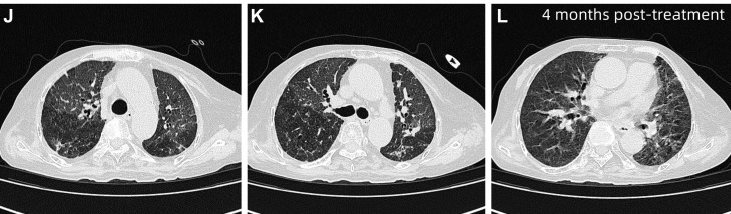

经过超过1个月的治疗后,患者呼吸困难较前改善,但未完全缓解。复查HRCT显示双肺弥漫性斑片状磨玻璃影伴小叶间隔增厚,呈“铺路石样”改变,并见局部空气支气管征。鉴于治疗改善不足,患者在行鼻导管吸氧(3L/min)的同时进一步行支气管镜检查检查,发现BALF呈乳白色,PAS染色阳性,提示肺泡内蛋白样物质沉积。

图3 患者治疗1个多月后HRCT,显示双肺弥漫性斑片状磨玻璃影伴小叶间隔增厚,呈铺路石样改变(黄色箭头)

治疗4个月后对患者进行随访,HRCT显示双肺纹理略增粗,弥漫性磨玻璃影较前明显减轻。